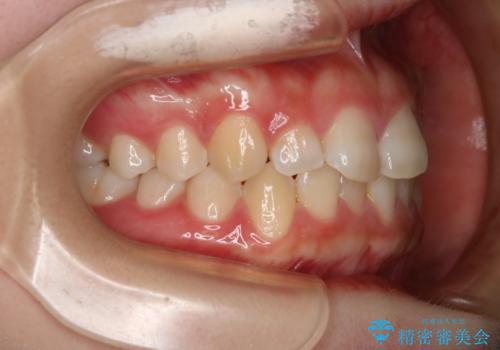

前歯のガタつきを治したい インビザライン・ライトパッケージ

- 前歯のガタつきの改善を主訴に来院された患者様です。

ガタつきによる上顎正中の空隙や歯の突出感も気にされていました。

費用を抑えたいとの事だったので歯の移動量なども考慮し、インビザライン・ライトパッケージでの治療を計画しました。